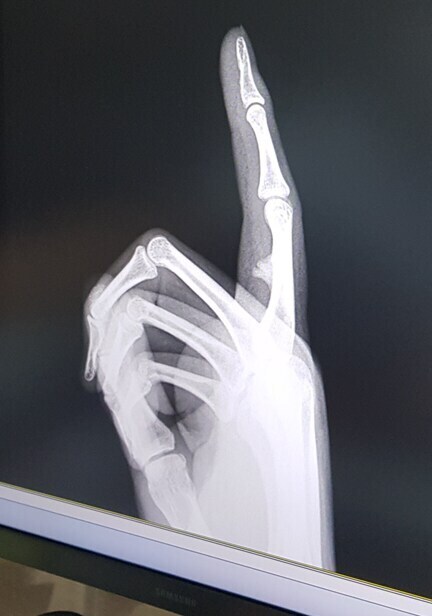

깁스 2주정도하고

검지는 4주정도 못 움직였었는데

녹슬고 틀어진 기계 부품 움직이는거 마냥 잘 안움직임

재활을 좀 빡쌔게 하면 근육통도 조금 생기더라